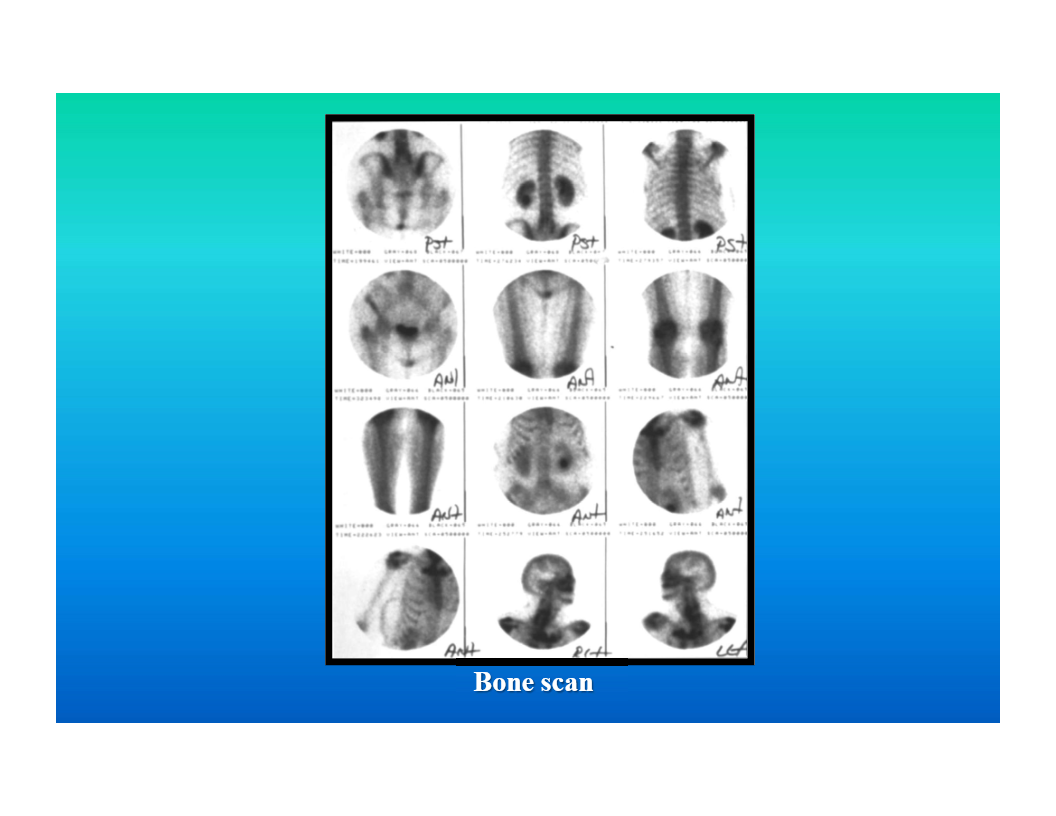

nuclear medicine

image generated by radioactive agent tagged to a tissue specific molecule

Tc99m frequently the radioactive agent

physiologic imaging rather than anatomic detail

examples - bone scan, hepatobiliary scan, tagged RBC study, cardiovascular studies

image descriptor is activity